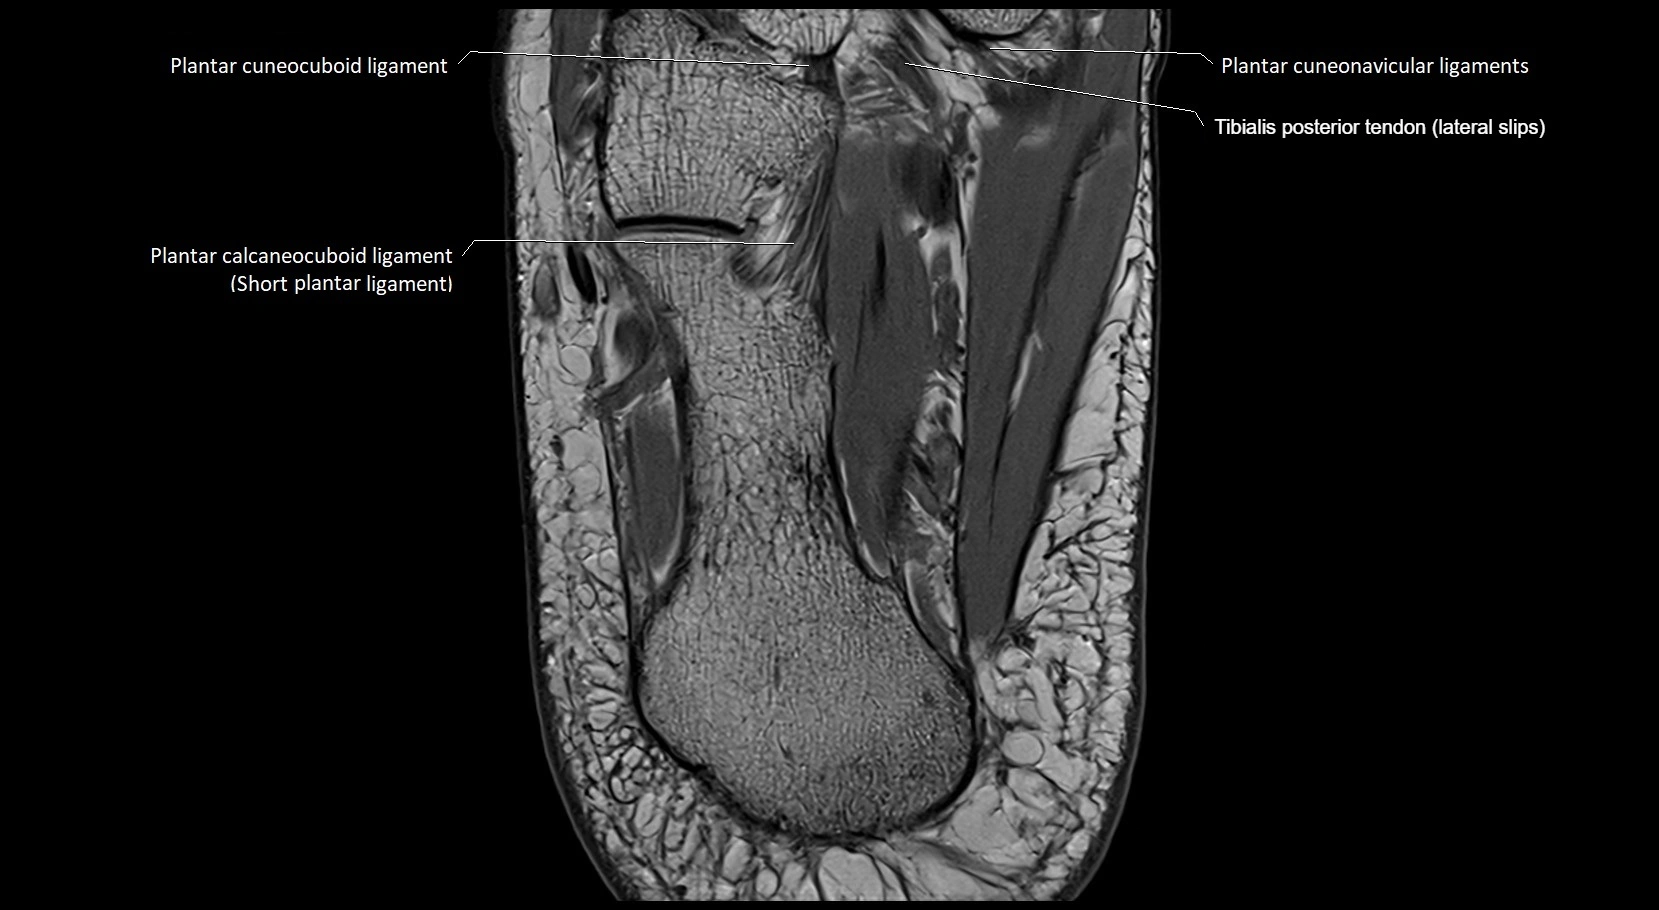

MRI image

image